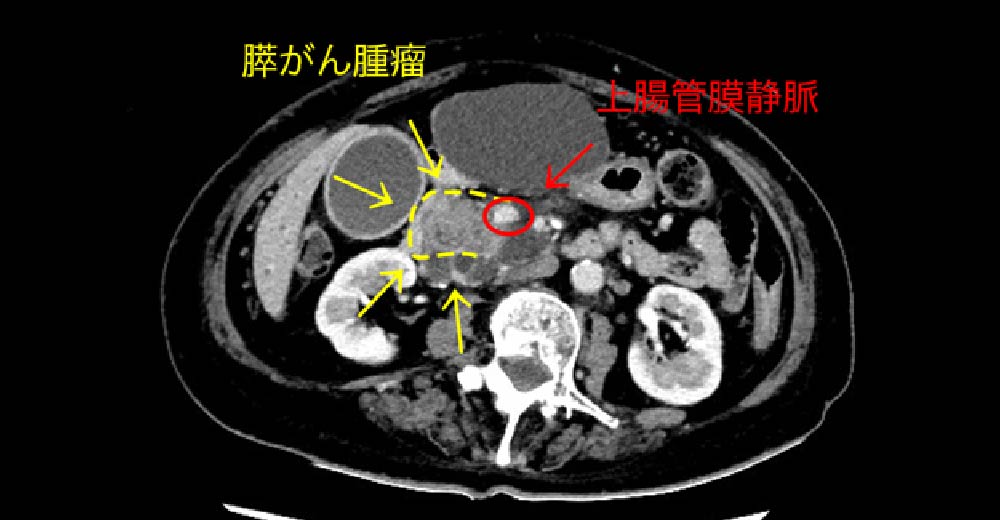

PV:門脈 SMA:上腸間膜動脈 SpV:脾静脈

2型糖尿病で、当院に転医された患者さんです。紹介元で1度も腹部エコーをされたことがなかったのですが、糖尿病の基本管理とおり定期腹部エコーにて、診断された“通常型膵がん”の症例です。背景疾患に、“糖尿病”がある場合は、常に新規“膵がん”発生を念頭において、外来観察する必要があります。

この症例では“膵がん”腫瘤が、生存に重要な“門脈”と“上腸管膜動脈”に近接しており、根治切除できるかどうかぎりぎりの患者さんです。切除できなければ、近代の医学においても予後は極めて不良です。

膵がん 膵がん

糖尿病診断契機に診断された、“膵がん”の1例です。

膵臓は臓器特性上、周囲に“生存に必須な血管が存在しており、進行した状態では、まず救命できません。糖尿病罹患患者さんでは、”膵がん“のリスクが高く、常に監視することが必要です。